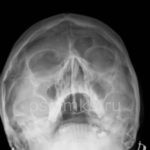

Если воспалительный процесс приводит к заполнению полости жидкостью, которая не может свободно вытекать, то на рентгеновском снимке появляется тень с горизонтальным уровнем.

На этой фотографии отчетливо видно количество жидкости в верхнечелюстных синусах. Медики называют этот рентгеновский эффект «молоко в стакане».

У больного обнаружен гайморит с обеих сторон. Чтобы убедиться в правильности диагноза, проводится рентген в двух проекциях: прямой и боковой. Если на обоих изображениях виден уровень накопившейся жидкости, то диагноз гайморита не подлежит сомнению.

Если на изображении, помимо уровня жидкости, обнаруживаются круглые затемнения в верхней части синуса, это может свидетельствовать о возможном появлении новообразований, таких как кисты, опухоли или полипы. В таких случаях проводится контрастная рентгенография, компьютерная томография с пошаговыми срезами и другие методы исследования, которые помогут определить природу новообразований.

Почти всегда при гайморите на рентгене (фото 6) обнаруживается характерное изображение, напоминающее молоко в стакане: в черных пазухах видно белое инфильтративное содержимое. Рентгеновский снимок пазух носа при гайморите, в сочетании с диагностическими симптомами, помогает врачу поставить правильный диагноз. Однако при скоплении гноя при гайморите (фото внизу страницы), патологические тени округлой формы не наблюдаются.